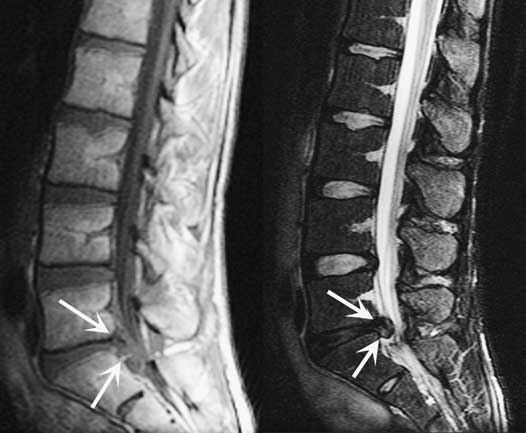

Многие пациенты не знают, к какому специалисту обратиться для диагностики и терапии этой патологии. Обычно они проходят обследование у нескольких врачей, что зависит от степени запущенности недуга. В процессе диагностики проводят полный осмотр, сбор анамнеза, магнитно-резонансную томографию и другие исследования для выявления основной причины заболевания.